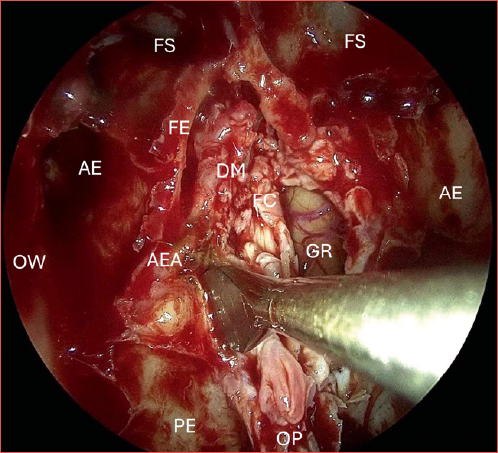

All patients underwent a fully endoscopic bilateral ethmoidectomy with sphenoidostomy and septectomy, resection of the middle turbinate, conchal lamina and complete exenteration of the olfactory cleft, with or without transnasal anterior skull base resection. When performed, endoscopic transnasal anterior craniectomy consisted in the resection of the entire lamina cribrosa, lateral lamella, crista galli, and overlying dura mater, as shown in the Cover figure. Abdominal fat graft with or without rectus abdominis fascia graft was used for the anterior skull base reconstruction. In cases with involvement of the medial part of the maxillary sinus, a medial maxillectomy was added to the procedure. The decision to resect the ASB was made prior to surgery according to the surgeon’s standard practice and the recommendation of the regional multidisciplinary oncology board. However, in some cases, intraoperative findings changed the approach. Evidence of tumour lysis or positive frozen sections on the skull base led to the resection of the ASB, when not previously anticipated. The retrospective determination of whether frozen sections were performed as a systematic margin assessment or in response to suspicion of tumour invasion was not possible. Therefore, these cases were excluded from the analyses. Thus, the study only included cases that were considered radiologically, clinically and surgically free of tumour involvement of the skull base.